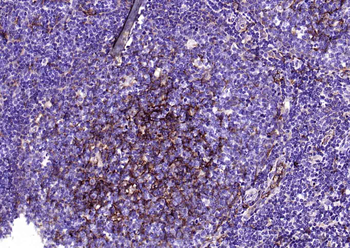

100 μl, 200 μl, 50 μl - RORC Rabbit Polyclonal Antibody [orb6888]Featured

FC, ICC, IF, IHC-Fr, IHC-P, WB

Human, Mouse, Rat

Bovine, Canine, Equine, Gallus, Porcine, Rabbit

Rabbit

Polyclonal

Unconjugated

50 μl, 100 μl, 200 μl - Featured